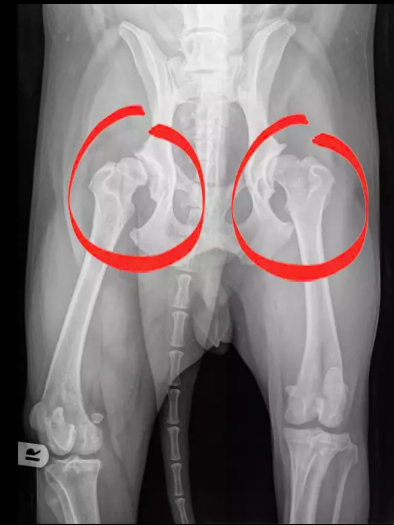

■ 診断:従来のレントゲン+最新のPennHIP評価

股関節形成不全の診断には、レントゲン(X線)検査が基本となります。しかし、成長期の犬では股関節の適合性が不安定なため、従来法では早期診断が難しいケースがあります。

そのため近年注目されているのが PennHIP(ペンヒップ) です。